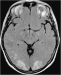

Abbildung 2: FLAIR-Sequenz Axiale Flair-Sequenz: hyperintense Signalveränderungen beidseits im okzipitalen Kortex, links auch temporal. |

Axiale Flair-Sequenz: hyperintense Signalveränderungen beidseits im okzipitalen Kortex, links auch temporal. |